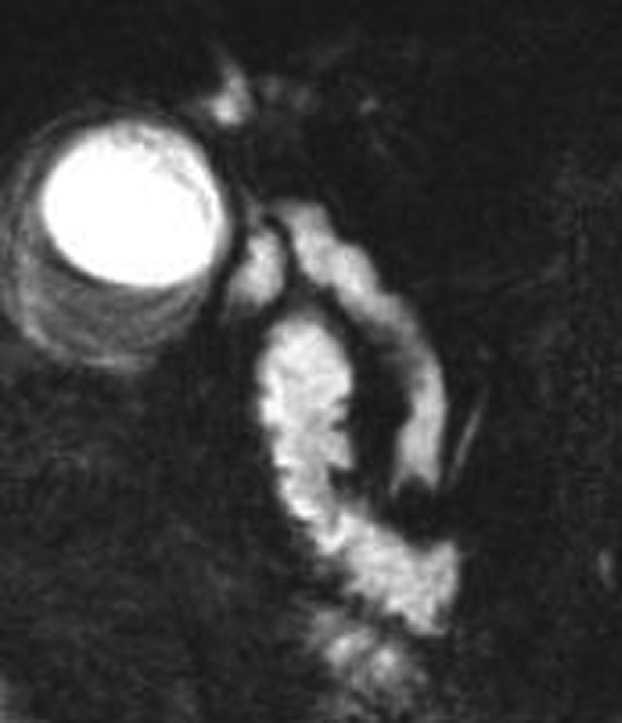

Mujer de 87 años que ingresa en el servicio de cirugía por ictericia, colangitis y pancreatitis aguda. Se instauró tratamiento con sueroterapia y antibióticos, que consiguió la estabilización hemodinámica de la paciente. En una colangiopancreatografía por resonancia magnética (fig. 1) se observó un defecto de repleción en el colédoco distal. Con la intención de desobstruir la vía biliar, se realizó una colangiopancreatografía retrógrada endoscópica (CPRE), empleando sedación consciente con midazolam y dolantina. En la endoscopia, la ampolla de Vater se encontró muy abultada, con un orificio en el que parecía entreverse una coledocolitiasis (fig. 2). Se realizó una esfinterotomía biliar amplia (fig. 3) y se extrajo una coledocolitiasis de 13 mm de diámetro máximo, que estaba impactada en la ampolla (fig. 4). La evolución de la paciente fue satisfactoria.

Fig. 4